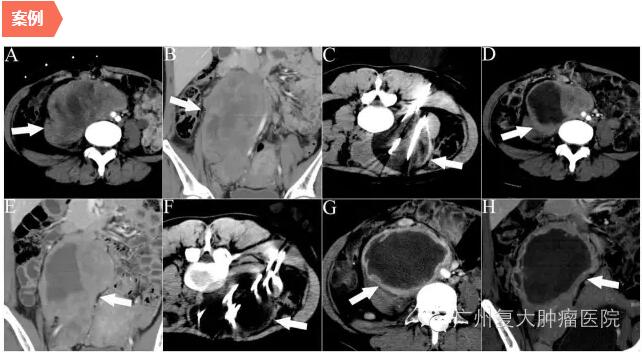

图示一位32岁女性患者,腹胀腹痛1个月,复发性后腹腔软组织肉瘤,接受两次冷冻消融。图中白箭头指示病变,白线指示冷冻探针,探针周围暗区系冰球。 A、B分别显示横断和冠状面增强CT上病变,同时显示主动脉矢状面; C 第一次冷冻消融,使用11根探针; D、 E第一次冷冻后1个月增强CT横断和冠状面,分别显示病变坏死、缩小; F第二次冷冻,使用10 根探针; G、H. 分别显示第二次冷冻后1个月增强CT的 横断和冠状面,肿瘤明显坏死和缩小。